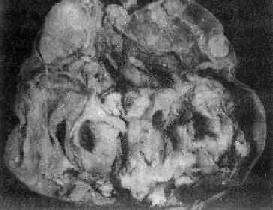

肉眼观,肿瘤多为囊性、中等大小,表面光滑,囊内含毛发团及皮脂样物(图13-22)。囊壁较厚,内侧常有一处突起的结节或我称头节,表面被覆鳞状上皮,结节内常有毛发、牙或骨质等。肿瘤多数为单房。镜下,可见到三胚层各种类型的成熟组织,其中以皮肤、皮脂腺、汗腺、毛囊及脂肪最多见;其次为软骨、神经胶质、神经细胞、骨及呼吸上皮;其他如甲状腺、胃肠上皮及牙等较少见。

图13-22 卵巢囊性畸胎瘤

囊内充满含有毛发的黄色油脂样物